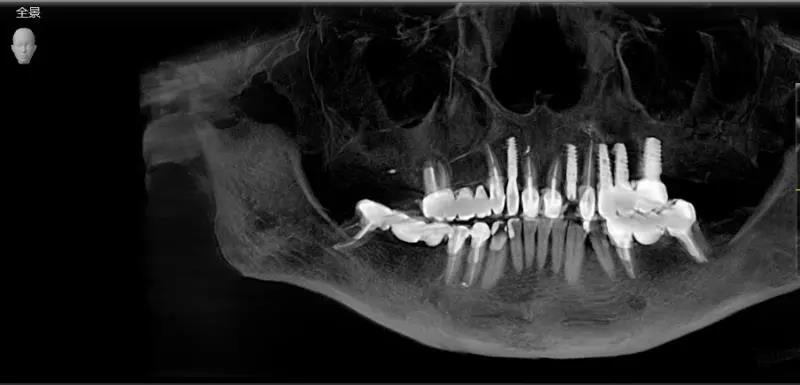

好的种植牙是可以让您沿用一生的,这意味着从种植术前的检查开始就要进行一系列精准地测量与保障。

医疗技术

海德堡联合口腔重新定义德国种植牙标准,在UNIC全息数字化种植中心将复杂的种植流程串连形成数字化闭环,提高种植品质,将误差减少到更小,维护术后种植体稳定性较强、成活率较高。

海德堡联合口腔引进全套德国口腔设备,严格执行口腔标准,透明、公开、优质的诊疗环境,给患者建立终身档案,长期享受医疗跟踪服务,力求不断从细节出发提升用户诊疗体验。